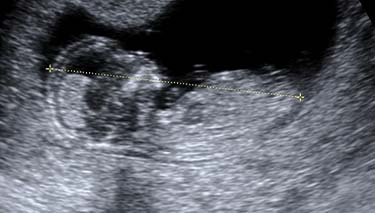

- Measurements of your baby's head, biparietal diameter, length and a measurement of their femur (long bone in the thigh) will also be taken. These measurements are compared with the average for babies of the same gestation.